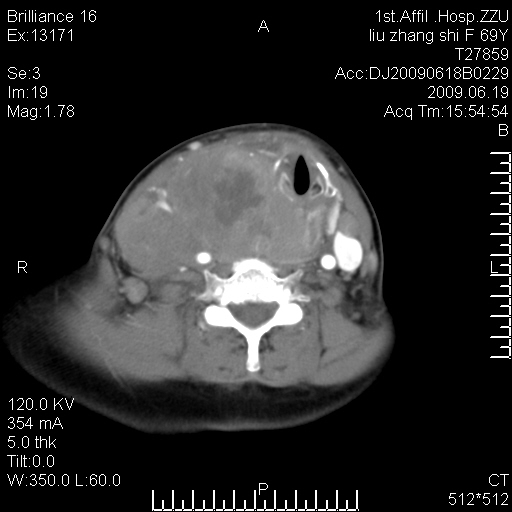

标题: CT26782:女,69岁,颈部占位,3天后公布病理结果。

【病理证实系列】女,69岁,颈部占位,有病理结果,3天后公布。(由于病例时间较久,临床资料不全,请网友见谅)本系列将有几百种常见、少见及罕见病例,均经病理证实。病例资料来自郑州大学第一附属医院。与网友共享,本人有空就发。

甲状腺癌并颈部淋巴结转移。感谢楼主的良苦用心,谢谢。

甲状腺癌并颈部淋巴结转移。

需与鼻咽癌鉴别!

支持甲状腺癌广泛侵及周围结构并颈部淋巴结转移。

鉴别:淋巴瘤、恶性神经源性病变、恶性纤维组织细胞瘤。

病理结果:颈部非霍奇金淋巴瘤。